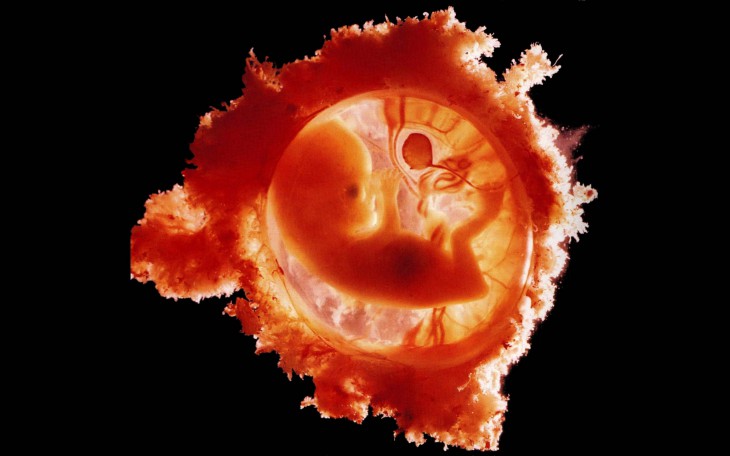

Что же такое плодное яйцо? Это оплодотворенная яйцеклетка, которая прикрепляется и превращается в плодное яйцо. Это еще не эмбрион, но уже зародыш, обладающий желточным мешочком, который будет обеспечивать его питанием до тех пор, пока он не станет более крепким.

Проще говоря, плодное яйцо — это еще не полностью сформированный эмбрион, который только что прикрепился к стенке матки, но при этом у него уже можно услышать сердцебиение. Сердце малыша бьется со скоростью от 150 до 230 ударов в минуту.

Постепенно прикрепленная к стенке матки оплодотворенная яйцеклетка будет расти и развиваться, превращаясь в эмбрион, который приобретет характерную форму, напоминающую букву С. У плода начнут формироваться ручки и ножки.